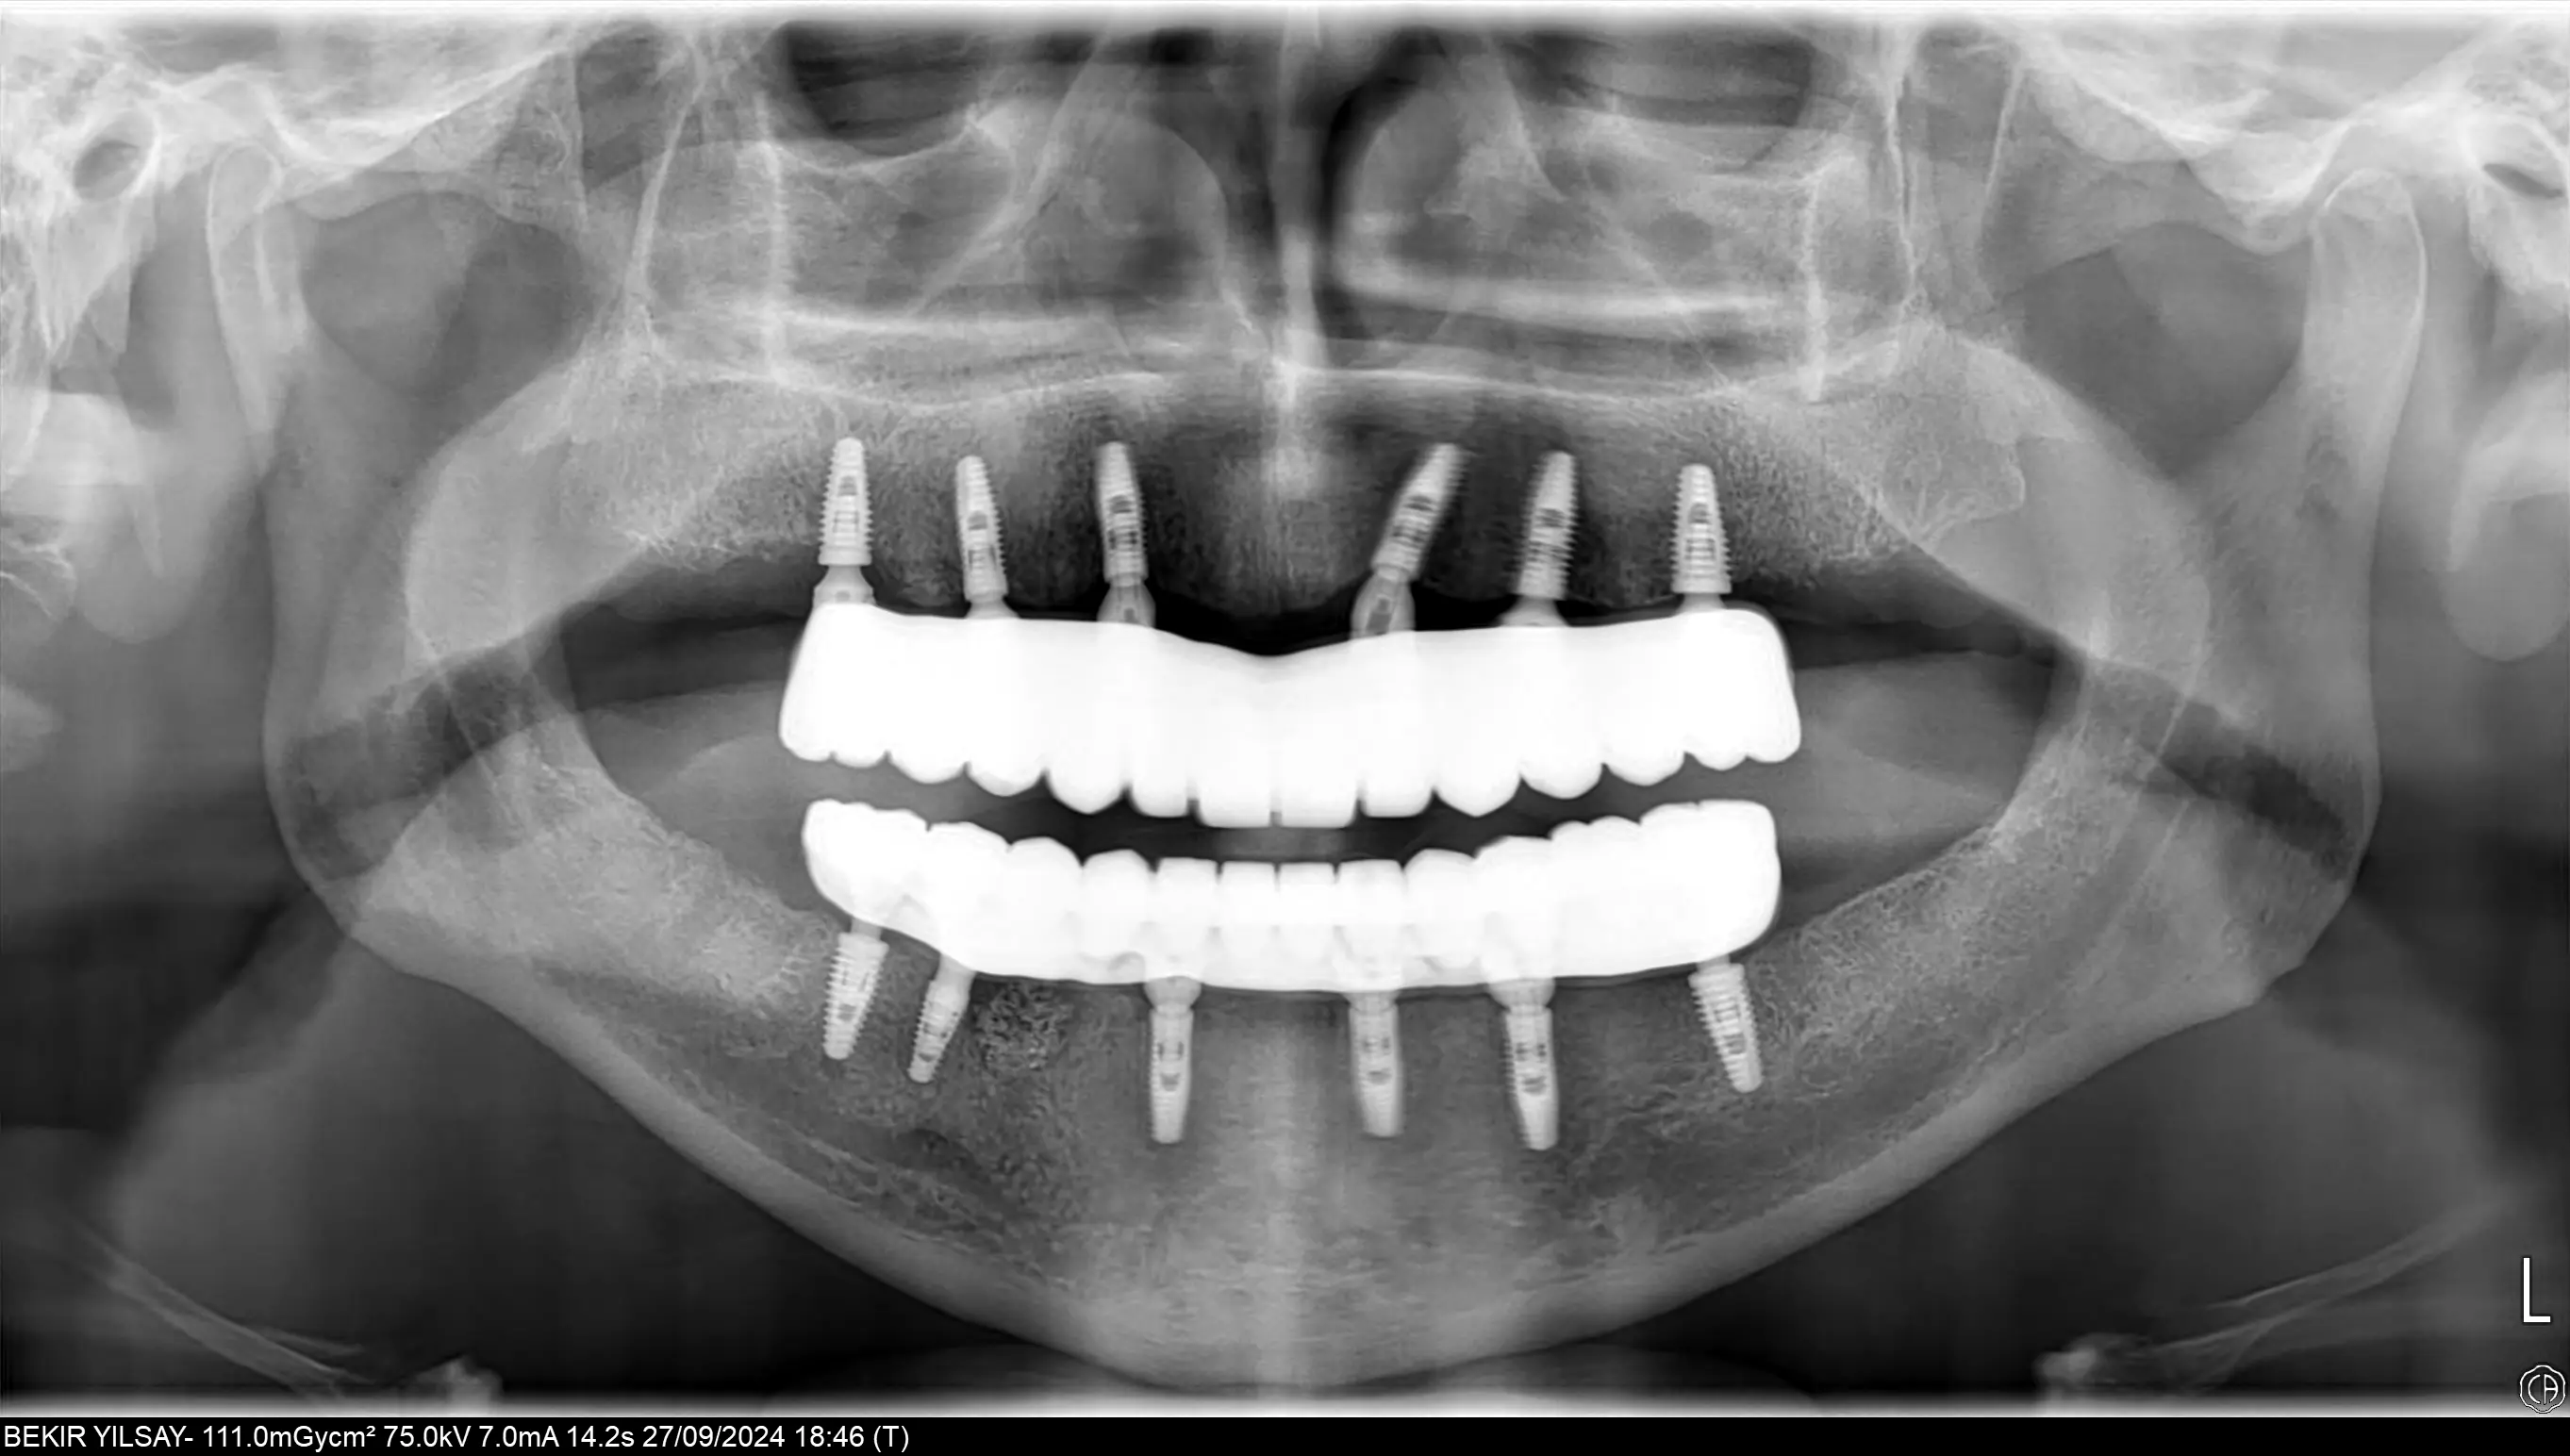

Unlike traditional removable dentures, All-on-6 implants are fixed, meaning they do not slip or shift. They offer the feel and function of natural teeth, allowing you to eat, speak, and smile with confidence. Additionally, implants help preserve jawbone density, preventing bone loss and maintaining facial structure over time. With their natural aesthetics, long-lasting durability, and high patient satisfaction, All-on-6 implants are a transformative solution to restore both the function and beauty of your smile.

At Attelia, our All-on-6 restorations are supported by a titanium frame that provides superior durability and ensures chewing forces are distributed equally across all six implants. This enhances patient comfort and guarantees long-term success. To increase precision and functionality, we use multi-unit abutments on each implant, ensuring optimum angles, alignment, and a more natural bite.

All-on-6 provides better stability, stronger biting force, and more even load distribution by using six implants per jaw instead of four. The use of multi-unit abutments and titanium frameworks further improves alignment and long-term success, making All-on-6 ideal for patients seeking maximum support and durability.